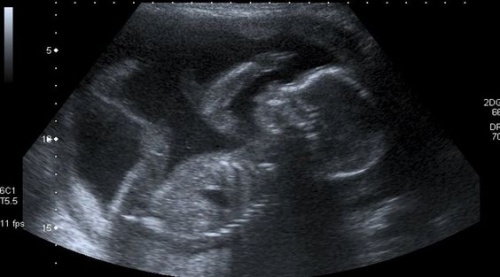

For the next nine months, she will have to settle for fuzzy ultrasound images on a black-and-white screen before she can see her son or daughter face to face and discover the color of her skin, hair and eyes.